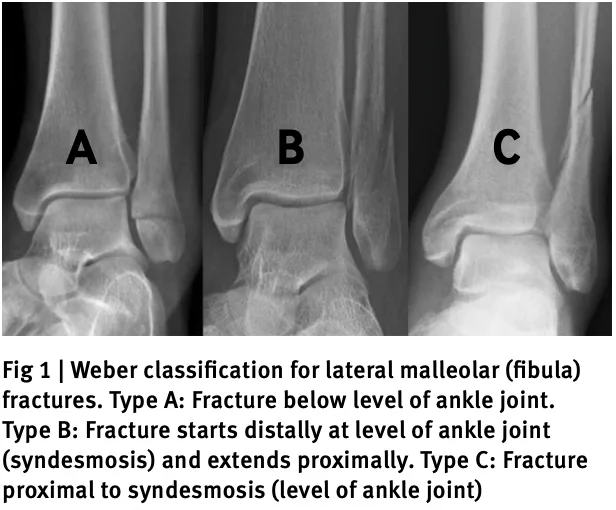

Type Aは, 足関節より遠位の骨折.

Type Bは, 骨折線が足関節の遠位から近位に達する斜骨折.

Type Cは, 足関節より近位での骨折.

X線写真の結果, 外くるぶし(外果)の骨折(Weber分類 Type B)と診断.